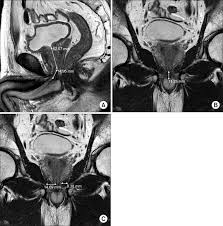

Strictly sagittal to the body axis. Prostate mri has become an increasingly frequent examination faced in daily radiological practice and is usually acquired as either multiparametric or biparametric mri of the prostate. The coronal view is from the top, showing the left and right sides of the gland.

• haste (axial, coronal, sagittal) • high resolution t2 (axial, coronal.